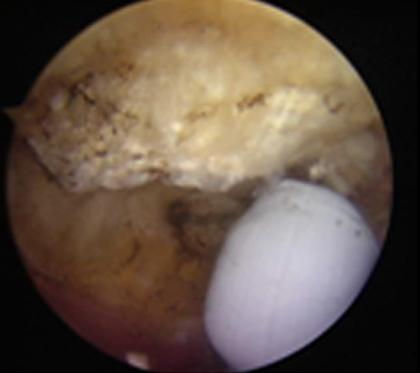

การรักษาโดยการผ่าตัดผ่านกล้องไหล่ ถือเป็นมาตรฐานการรักษาโรคของข้อไหล่ที่ยอมรับกันทั่วโลก นอกจากสามารถให้การวินิจฉัยแล้วยังเป็นการรักษาในคราวเดียวกัน กรณีที่เหมาะสมต่อการผ่าตัดส่องกล้องข้อไหล่ คือโรคของข้อไหล่ที่รักษาด้วยวิธีอนุรักษ์นิยมอย่างเต็มที่แล้ว ซึ่งประกอบด้วย การรับประทานยาแก้ปวด เช่น พาราเซตามอล, ยาลดอาการอักเสบที่ไม่ใช่สเตียรอยด์ และยาคลายกล้ามเนื้อ ร่วมกับกายภาพบำบัดอย่างเต็มที่แล้วไม่ได้ผล เป็นเวลาอย่างน้อย 3-6 เดือน จึงพิจารณานำวีธีการผ่าตัดผ่านกล้องมารักษา ซึ่งจะทำการเปิดแผลขนาด 0.5 - 1 ซ.ม. ประมาณ 2-3 แผล เพื่อใส่กล้องขนาดประมาณ 4 มิลลิเมตร ใส่น้ำเกลือเข้าไปในข้อเพื่อขยายพื้นที่ในการผ่าตัด และใส่อุปกรณ์การผ่าตัดเพื่อทำการรักษา พบว่าผลการรักษาไม่แตกต่างจากการรักษาโดยการเปิดแผล แต่กลับฟื้นตัวได้เร็วขึ้น

ตัวอย่างการผ่าตัดผ่านกล้องรักษากระดูกงอกทับเส้นเอ็นหัวไหล่